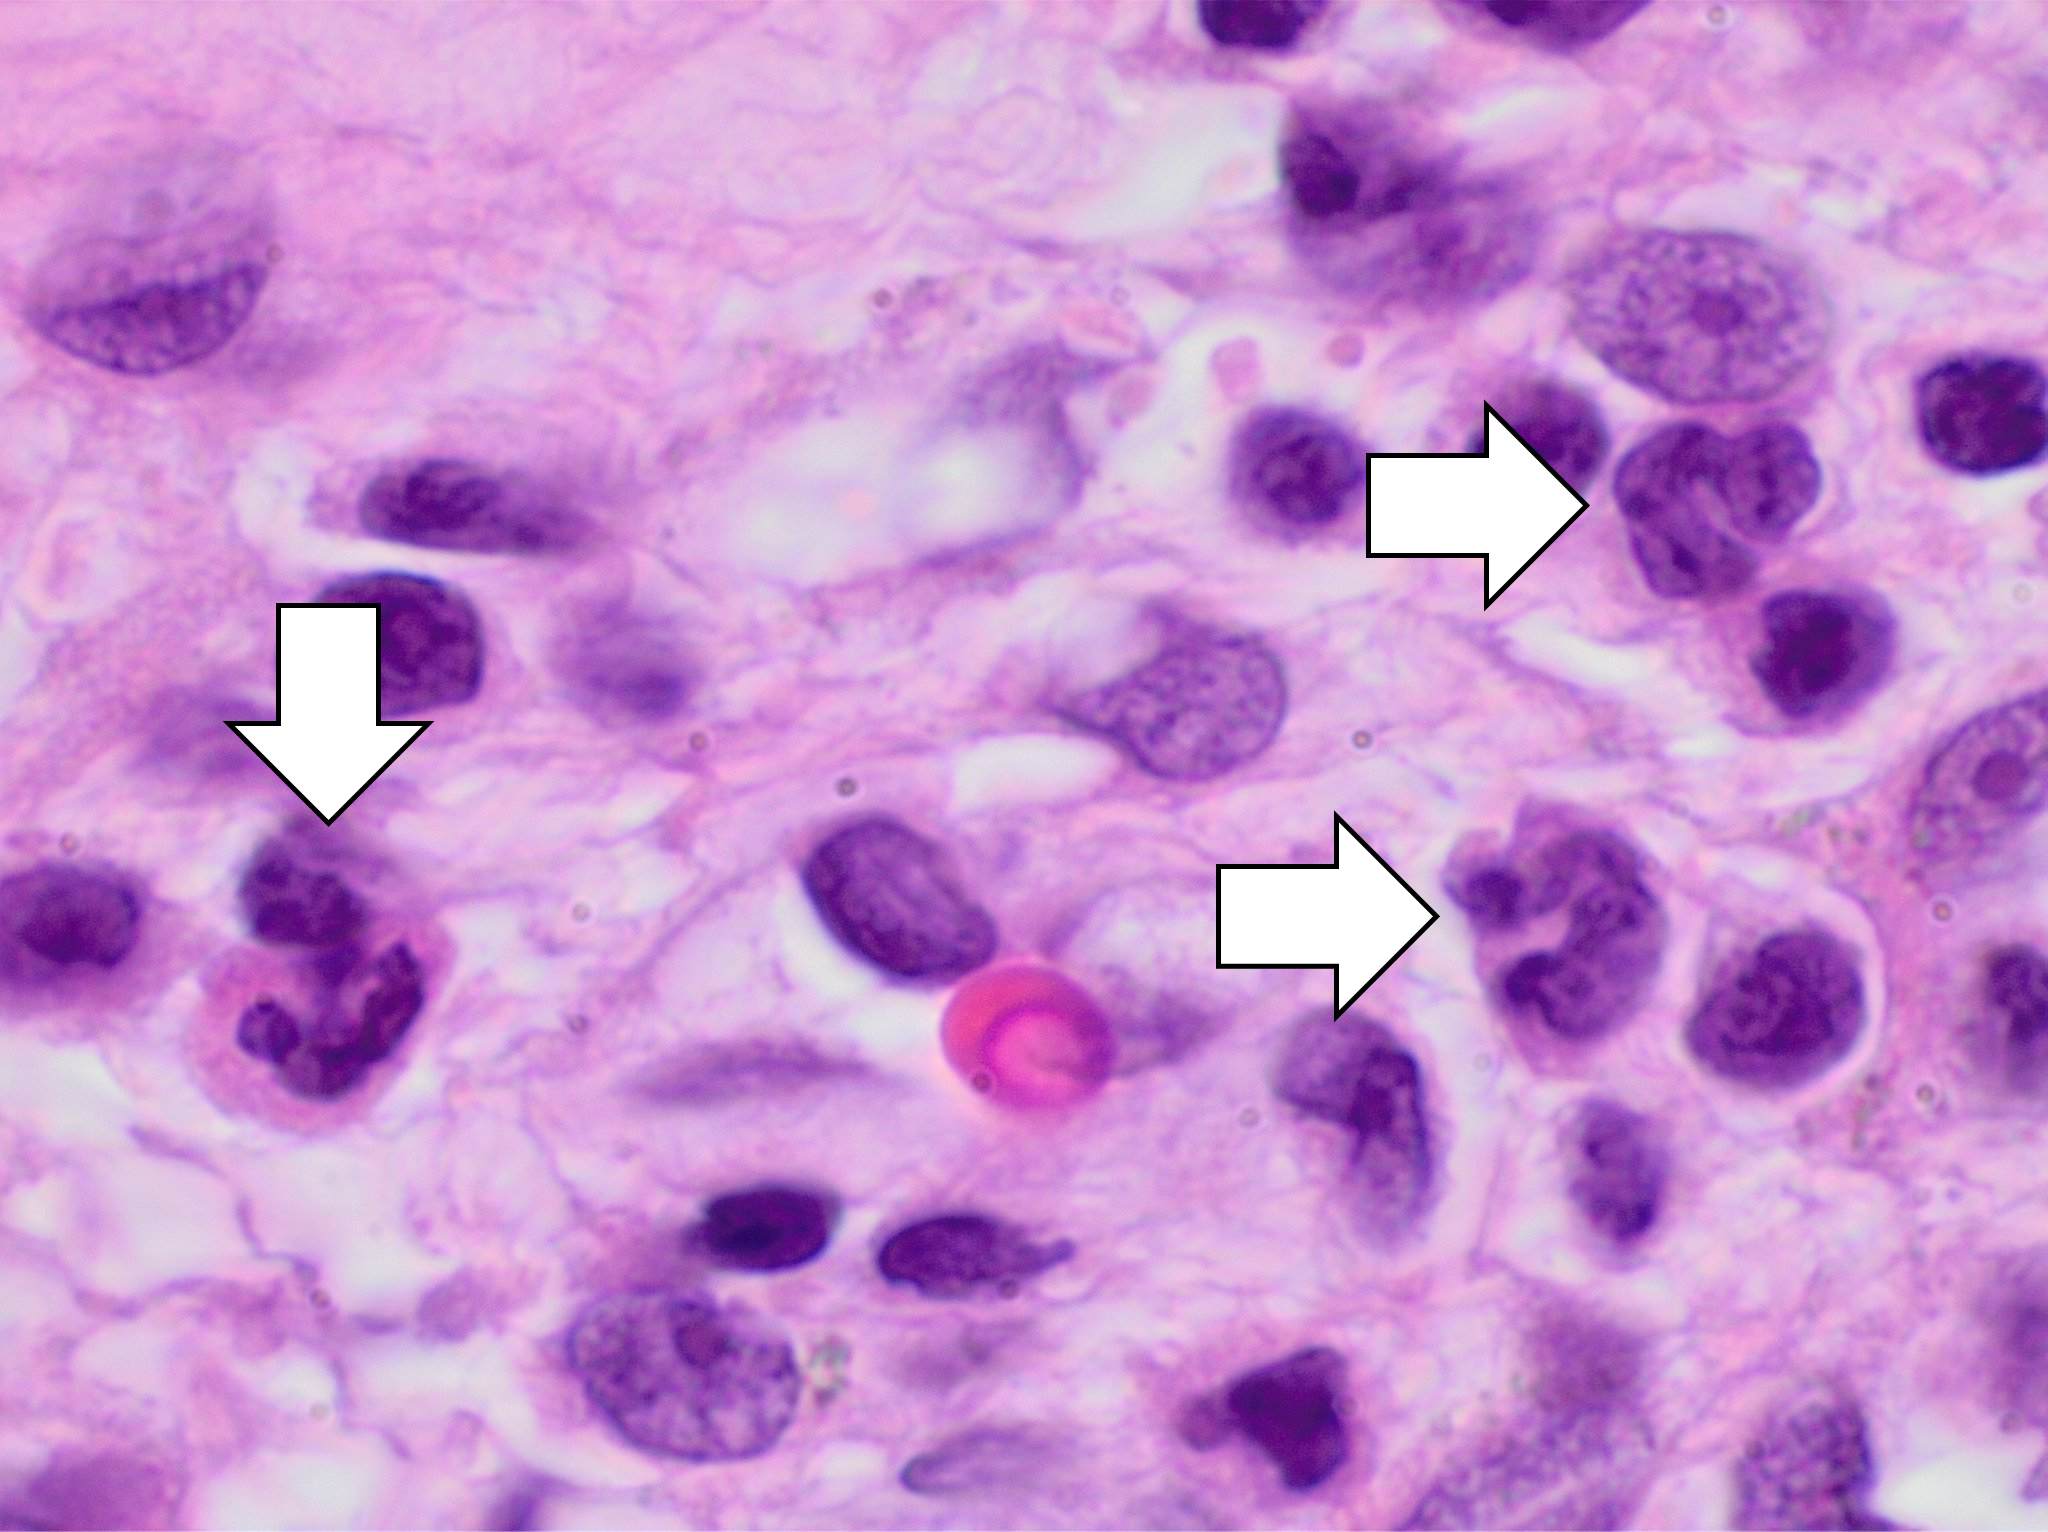

Фотографии объектов и элементов, связанных с цифрой 3

Раздел: Картинки на заметку